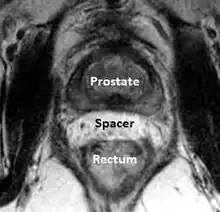

A new method to reduce rectal radiation injury in prostate cancer patients involves the use of an absorbable spacer placed between the prostate and rectum.

MRI showing hydrogel spacer pushing the rectum away from the prostate during radiotherapy.

Such spacers are commercially available in some regions and are undergoing clinical trials in others.[30] By temporarily altering the anatomy these products have the potential to allow for improved cancer targeting while minimizing risk to neighboring healthy tissues. Prostate rectum spacers should be compatible with all prostate cancer radiotherapy treatments including 3D conformal, IMRT and stereotactic radiation and brachytherapy.